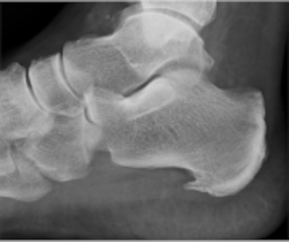

Stoßwellentherapie Fersensporn

• Fersensporn (Plantarasziitis) und Fersenschmerz

• Achillissehnenentzündung (Achillodynie)